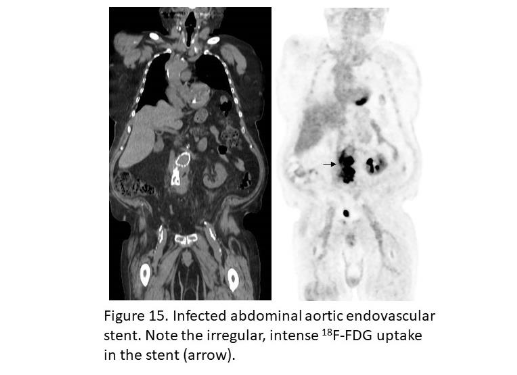

The sensitivity and specificity of ¹⁸F-FDG for prosthetic vascular graft infection range from 88–100%⁵²,⁵³. Like any foreign body, prosthetic vascular grafts can incite an inflammatory reaction, which can lead to increased ¹⁸F-FDG activity, even in the absence of infection. Familiarity with normal ¹⁸F-FDG uptake patterns around these grafts and those associated with foreign body reaction and infection improves the accuracy of test (Figure 15)⁵⁴–⁵⁷.

Figure 15.

Infected abdominal aortic endovascular stent. Note the irregular, intense ¹⁸F-FDG uptake in the stent (arrow).